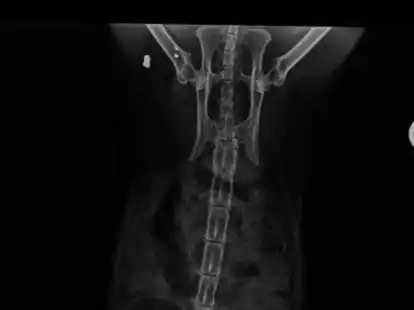

Die im Gewebe eingekapselten Geschosse kamen zufällig beim Röntgen ans Licht.

BESORGTE KATZENBESITZER Wer schießt mit dem Luftgewehr auf Zetels Katzen?